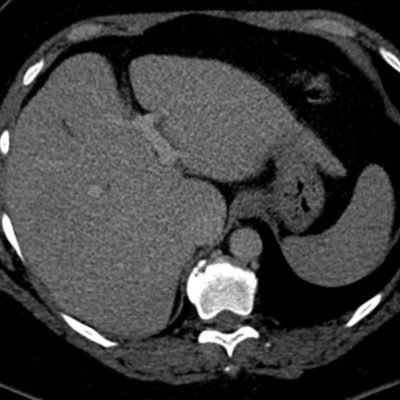

El estudio se complemento con resonancia magnética, donde se demostró la presencia de múltiples imágenes focales hepáticas confluentes con disminución de la señal en secuencias fuera de fase, no mostrando alteración de la señal en secuencias potenciadas en T2, sin signos de restricción al pulso difusión ni refuerzos anómalos luego de la administración de contraste endovenoso, estos hallazgos confirman la sospecha de esteatosis focal multinodular (fig. 5, 6 y 7).

Independiente de su patrón de presentación, no condicionan cambios del parénquima luego de la administración de contraste endovenoso, no obstante igualmente se utiliza el gadolinio como medio de contraste para descartar otras entidades que puedan simular esta patología. La TC no suele aportar datos concluyentes cuando los focos de esteatosis son de pequeño tamaño y de bajo contenido graso, no logrando una adecuada diferenciación en su atenuación.7-8 (fig. 14)